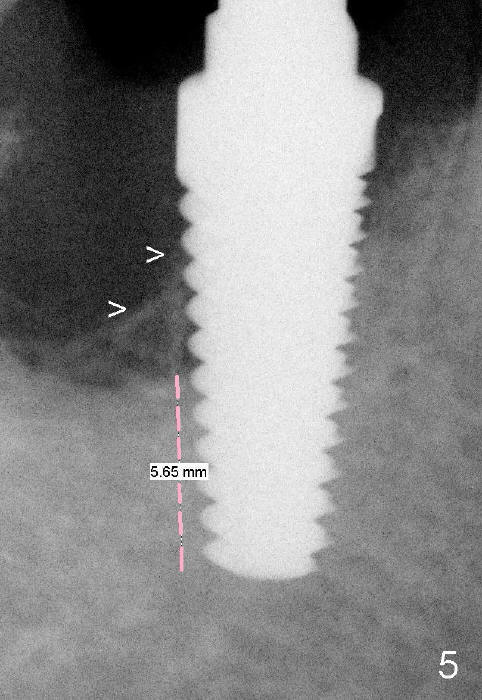

The osteotomy formed by osteotomes and tap so far deviates lingual. The position of the osteotomy is corrected by using 1.5 mm pilot drill and 3.5, 4.0, 4.5x17 mm tapered drills. It is followed by insertion of 5x17 mm tap, 6x17 mm tap (Fig.5 with more than 5 mm of the tap surrounded by solid bone) and 7x17 mm tap.